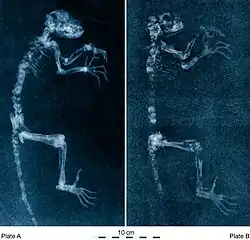

Industrial radiography is a method of non-destructive testing where many types of manufactured components can be examined to verify the internal structure and integrity of the specimen. Industrial Radiography can be performed utilizing either X-rays or gamma rays. Both are forms of electromagnetic radiation. The difference between various forms of electromagnetic energy is related to the wavelength. X and gamma rays have the shortest wavelength and this property leads to the ability to penetrate, travel through, and exit various materials such as carbon steel and other metals. Specific methods include industrial computed tomography.